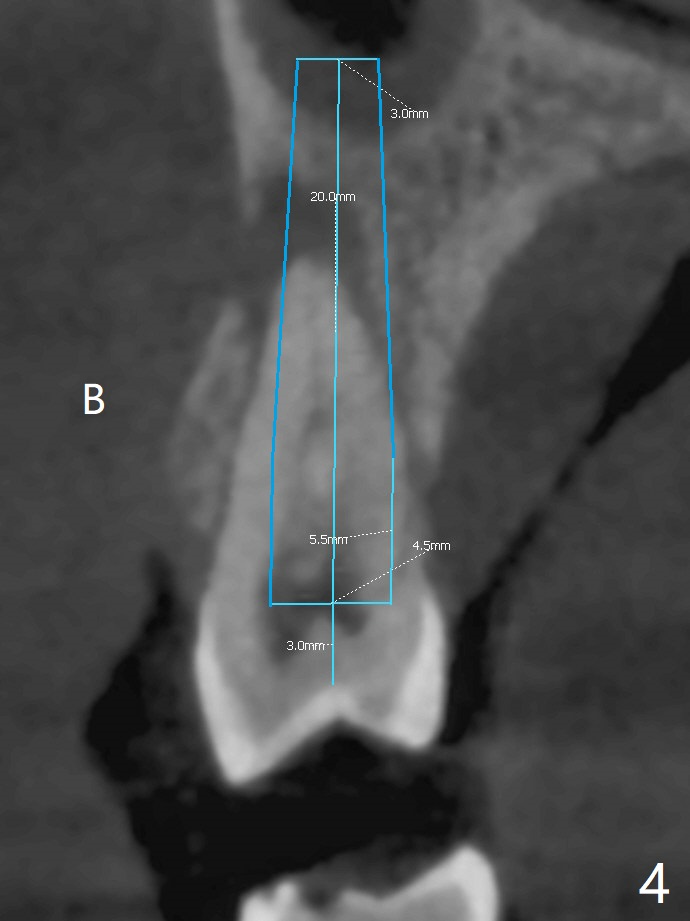

A 52-year-old woman had palatal periodontal infection at #2 a half month earlier (Fig.1,2), which was treated with Arestin. When she returns, the tooth #4 has palatal subgingival oblique fracture (Fig.3 <), interfering with mastication. Due to emergency, free hand immediate implant is planned. The buccal apical defect (Fig.3 *) will be repaired with PRF membrane (x1) and allograft after osteotomy (with gauze in place). A 4.5x20 mm tissue-level implant will be placed (Fig.4) instead of a bone-level one (Fig.5).